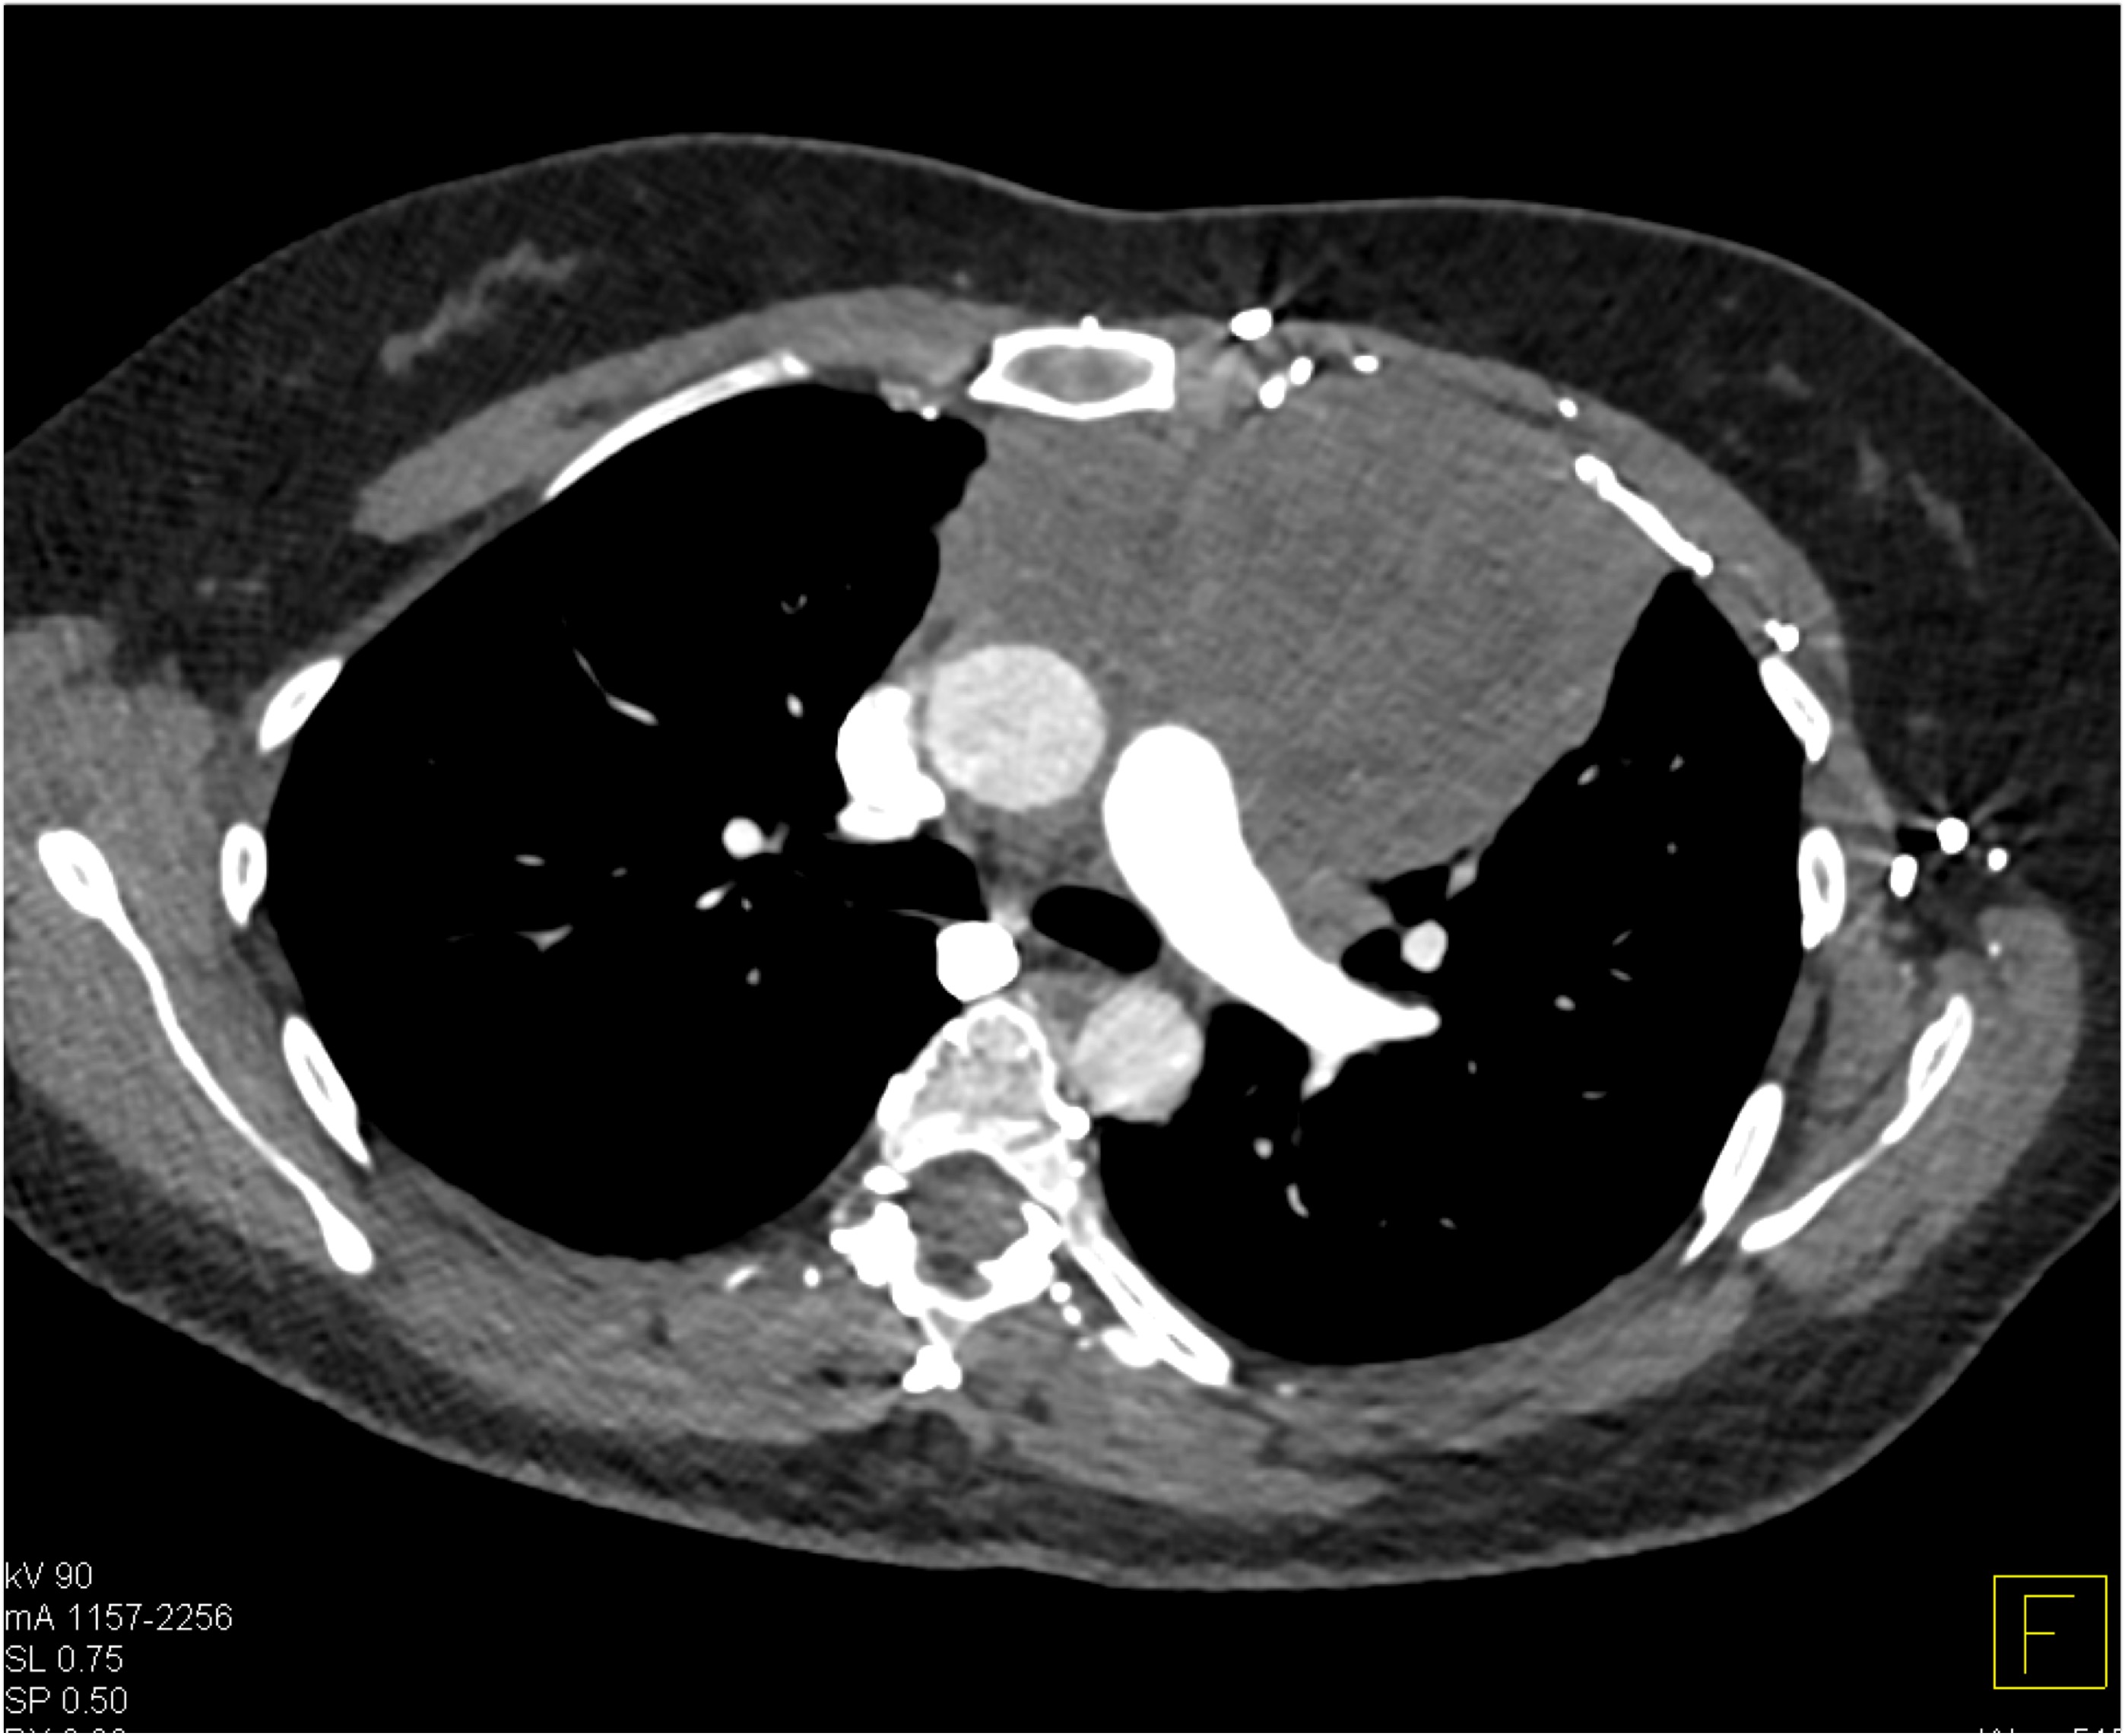

The most likely diagnosis in this 30ish year old with FUO is?

teratoma

thymoma

ectopic thyroid tissue

B-cell lymphoma